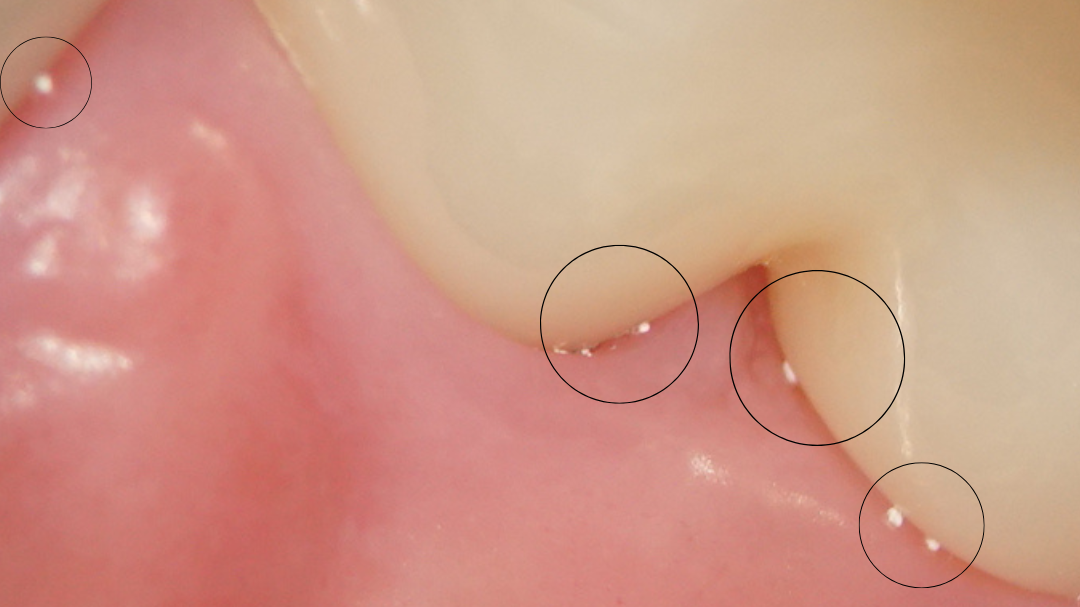

こちらは、当院のメインテナンスの3時間前に自宅で顆粒入りの歯磨き粉を用いて歯みがきをした患者様の口腔内の写真です。(マイクロスコープで撮影)

歯茎の際の部分に、白い粒が付いているのが見えます。歯みがきをしてから3時間も経っているのに、歯周ポケットの中に入り込んでしまっています。このまま排泄されずにずっと歯茎の中にいてしまったら、歯茎が下がり歯周病になってしまいます。